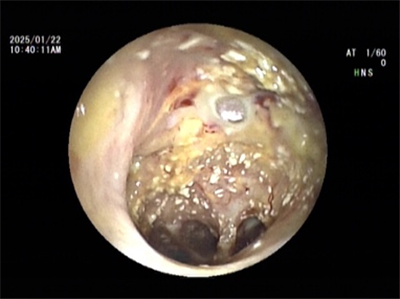

2024年12月18日,在王海龙主任的带领下,医疗团队凭借精湛的医术和丰富的经验,在支气管镜的精准引导下,将消融针准确插入肿瘤部位,运用圈套、冻切等方式对肿瘤组织进行消融。然而,由于肿物堵塞左主支气管开口,在使用电圈套及冷冻技术切除肿物的过程中,发现阻塞范围广泛,若进行完全冻融操作,时间过长且手术风险过高,因此,医疗团队先予以部分消融,解除了肿物对气道的阻塞。2025年1月22日,医疗团队为患者行第二次气管镜下冻融治疗,成功完全解除气管阻塞。术后,患者呼吸明显顺畅,各项生命体征平稳,恢复情况良好。